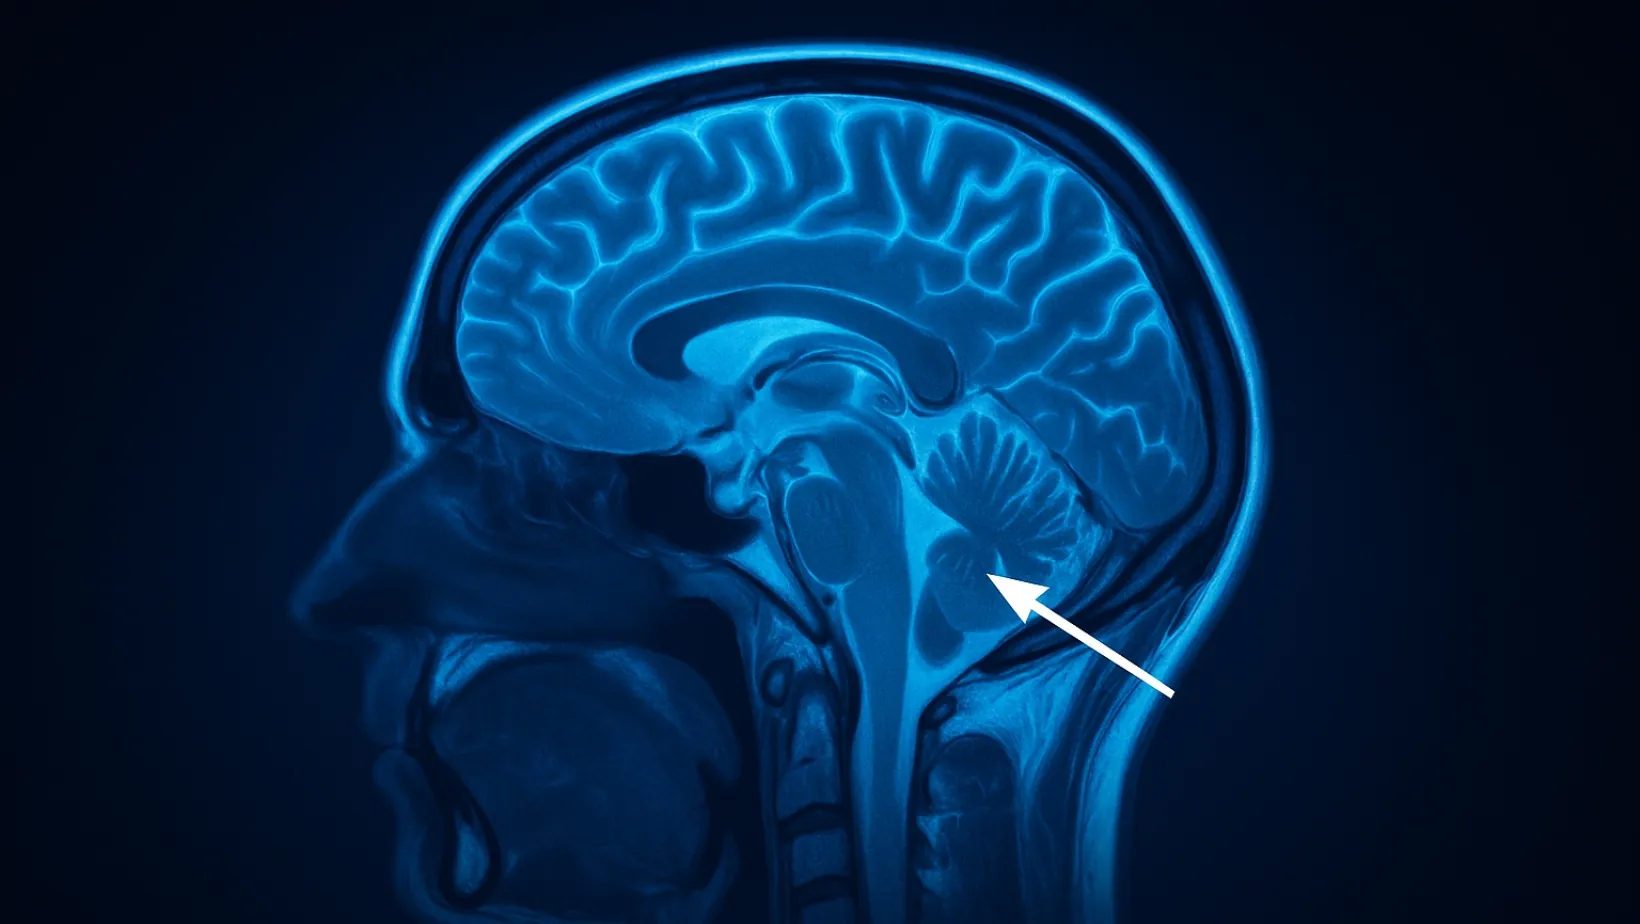

Basilar migraine is a rare but striking form of migraine that starts in the…